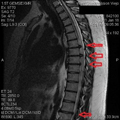

I’m not gonna give you guys a lesson in reading MRI Reports, so here’s the short version. (T# are different vertebrae – Google it)

T5-T6: 4 mm disc protrusion

T6-T7: 10-11 mm disc protrusion

T7-T8: 9 mm disc protrusion

T8-T9: 3-4 mm disc protrusion